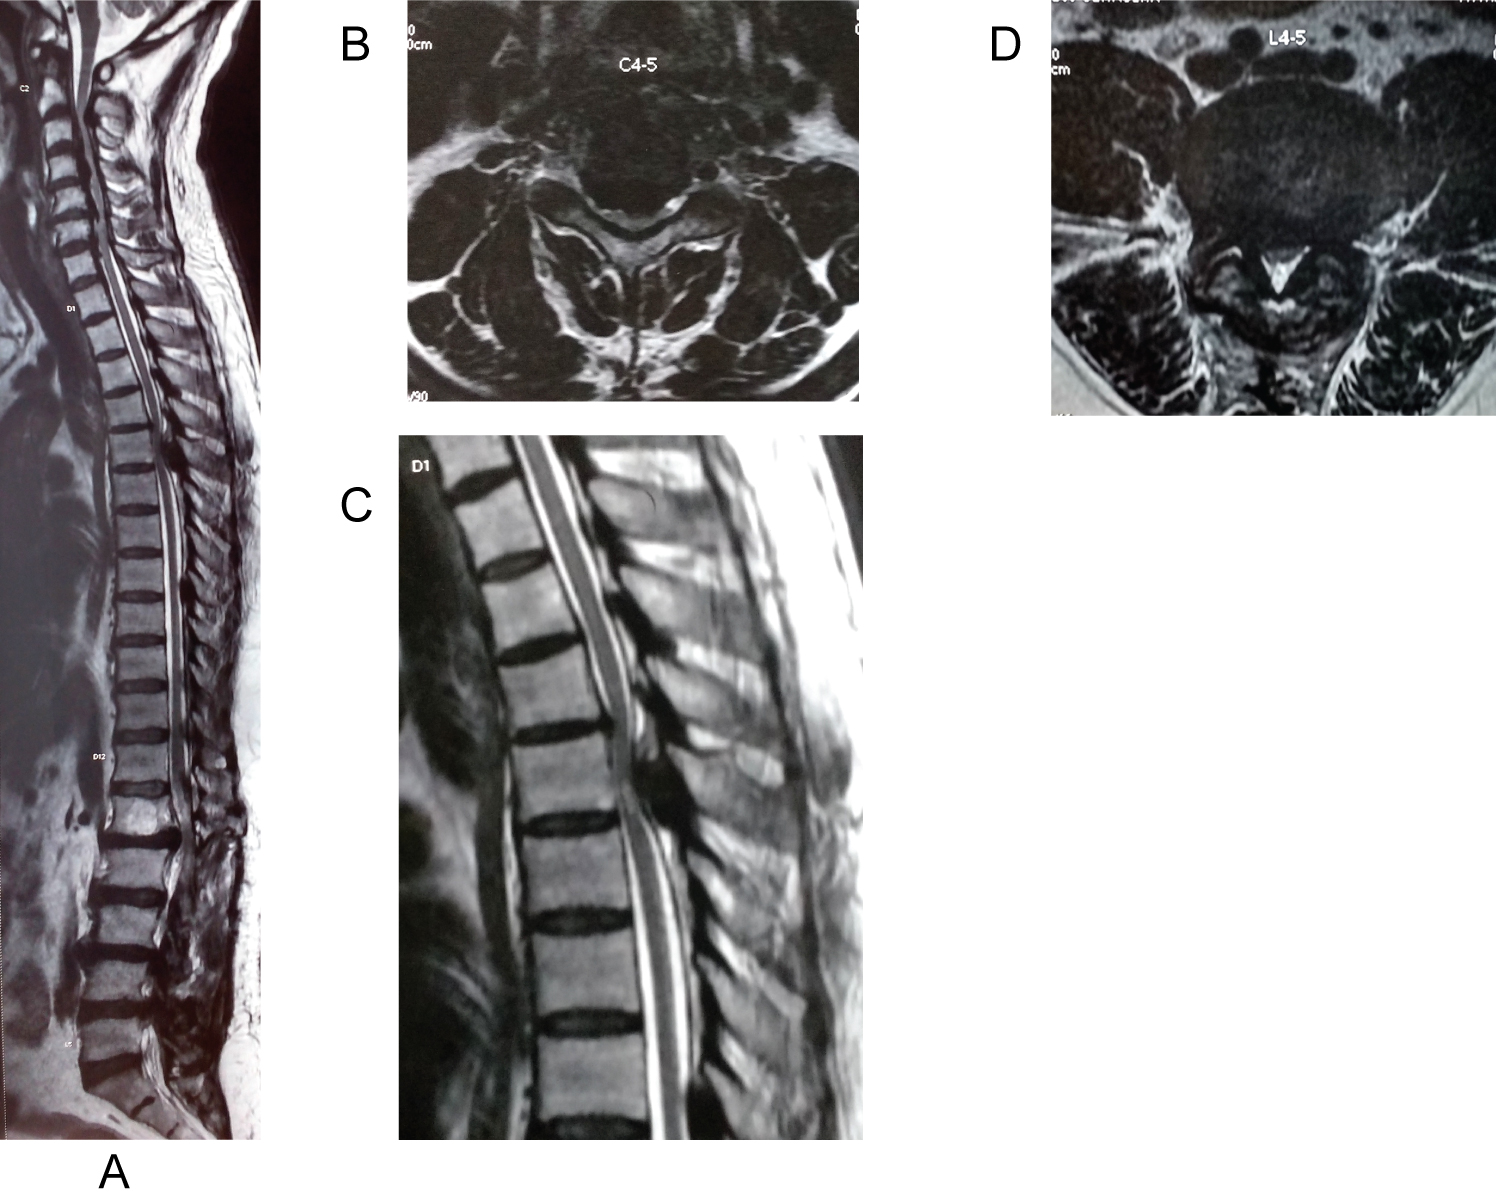

A 66-years-old male presented with low back pain and bilateral leg pain since 6 months and difficulty while walking since 2 months. He also complained of increased urinary frequency and urgency since 1 month. He had no previous history of trauma to back.

On examination, Power in both upper limbs was grade 5 and lower limbs was grade 4. Lower limbs were more spastic as compared to the upper limbs. Grip release test and fine activities of hand were normal. Upper limbs reflexes were exaggerated, in lower limbs, knee reflex was exaggerated and ankle reflex was diminished. Patient was a known hypertensive since 12 years and diabetic since 8 years and was on regular medications. MRI Cervical spine with whole spine screening revealed Triple-Region Spinal Stenosis. MRI of Cervical spine early cervical canal stenosis secondary to localised Ossified Posterior Longitudinal Ligament from C5-C7. Thoracic spine showed cord compression due to a disc protrusion and calcification at D7-8 with cord oedema. Lumbar spine severe had severe canal stenosis at L4-5 level.

Management: In view of normal upper limb power and normal fine activities, Patient was operated for posterior Lumbar and thoracic decompression in first stage. D7-8 Transforaminal fusion and L4-5 Transforaminal fusion was only was carried out in a same sitting by two spine surgeons simultaneously. Patient's nurick grade (grade3) did not worsen, upper limb power and fine activities remained normal, so patient has been kept on close watch for 1 year post-operatively and has not been operated for cervical decompression yet (Figure 4).

Figure 4: Whole spine sagittal cut showing TRSS at C5-C7, D7-8 and L4-5. Axial section at the level with maximum compression - cervical cord at C5-6, thoracic cord at D7-8, Lumbar spine at L4-5. View Figure 4